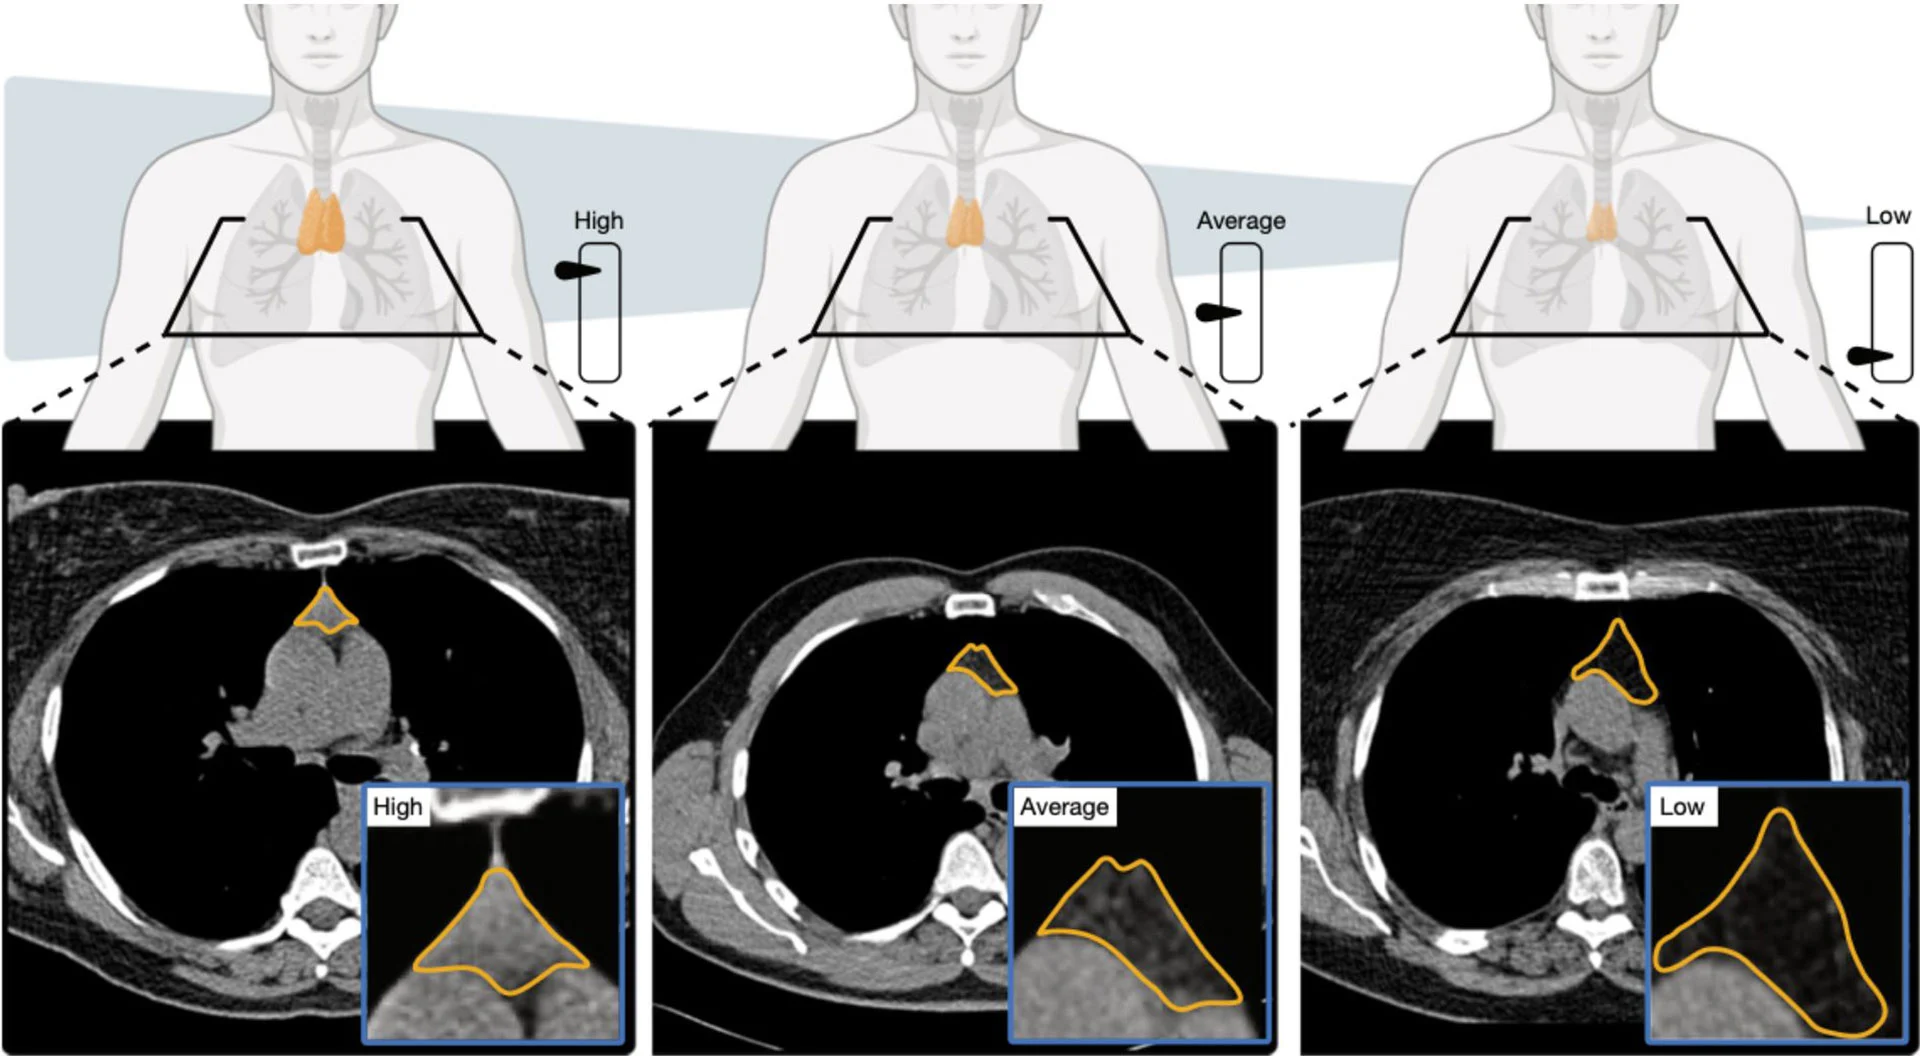

早期研究虽发现T细胞多样性与衰老、免疫功能下降有关,但大多依赖少量血液样本。而这项新研究分析了超过25,000名成年人(来自美国全国肺癌筛查项目)和2500多名参与者(来自长期健康人群队列弗雷明汉心脏研究)的数据。

研究人员通过测量胸腺大小、结构和组织状态,创建了一个“胸腺健康评分”。结果显示:

- 评分更高的人,死亡风险降低约50%

- 心血管疾病死亡风险降低63%

- 肺癌发生风险降低36%

在校正年龄和其他健康因素后,这些关联依然显著。